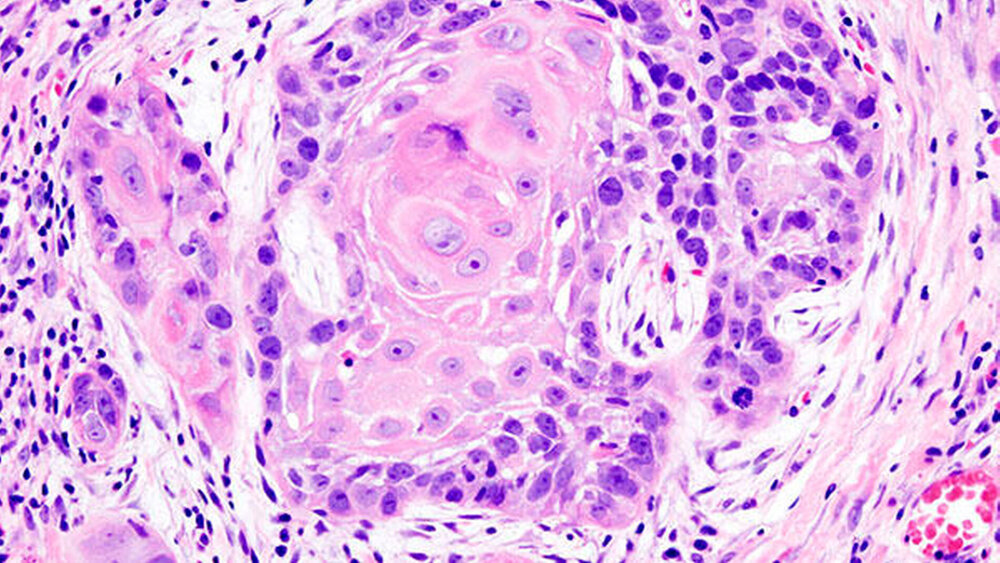

Finnische Forscher haben erstmals entdeckt, dass die Oberflächenzellen der Lymphgefäße bei Mundhöhlenkrebs Proteine ​​enthalten, die auf Zellteilung hinweisen und die Krankheitsprogression sowie die Sterblichkeit stark vorhersagen.

Das Forschungsteam der Universität Turku und des Forschungsprojekts InFLAMES untersuchte anhand von Proben aus Mundhöhlenkrebs-Frühstadien, die von etwa 300 finnischen Patienten stammten, die Eigenschaften verschiedener Abwehr- und Strukturzellen im Tumorgewebe. Durch die Analyse mehrerer unterschiedlicher Proteinmarker machten die Forscher die überraschende Entdeckung, dass einige Tumore eine höhere Anzahl proliferierender Lymphgefäße aufwiesen als normales Gewebe. Diese hohe Anzahl proliferierender Lymphgefäße sagte das Wiederauftreten des Krebses und die Sterblichkeit besser voraus als alle anderen bisher bekannten Risikofaktoren für Mundhöhlenkrebs.

Markerproteine sind die Hinweisgeber

Lymphgefäße sind normalerweise im Mund vorhanden, aber in einer gesunden Mundhöhle teilen sich ihre Zellen selten, und Markerproteine, die auf diesen Prozess hinweisen, sind normalerweise nicht zu sehen.